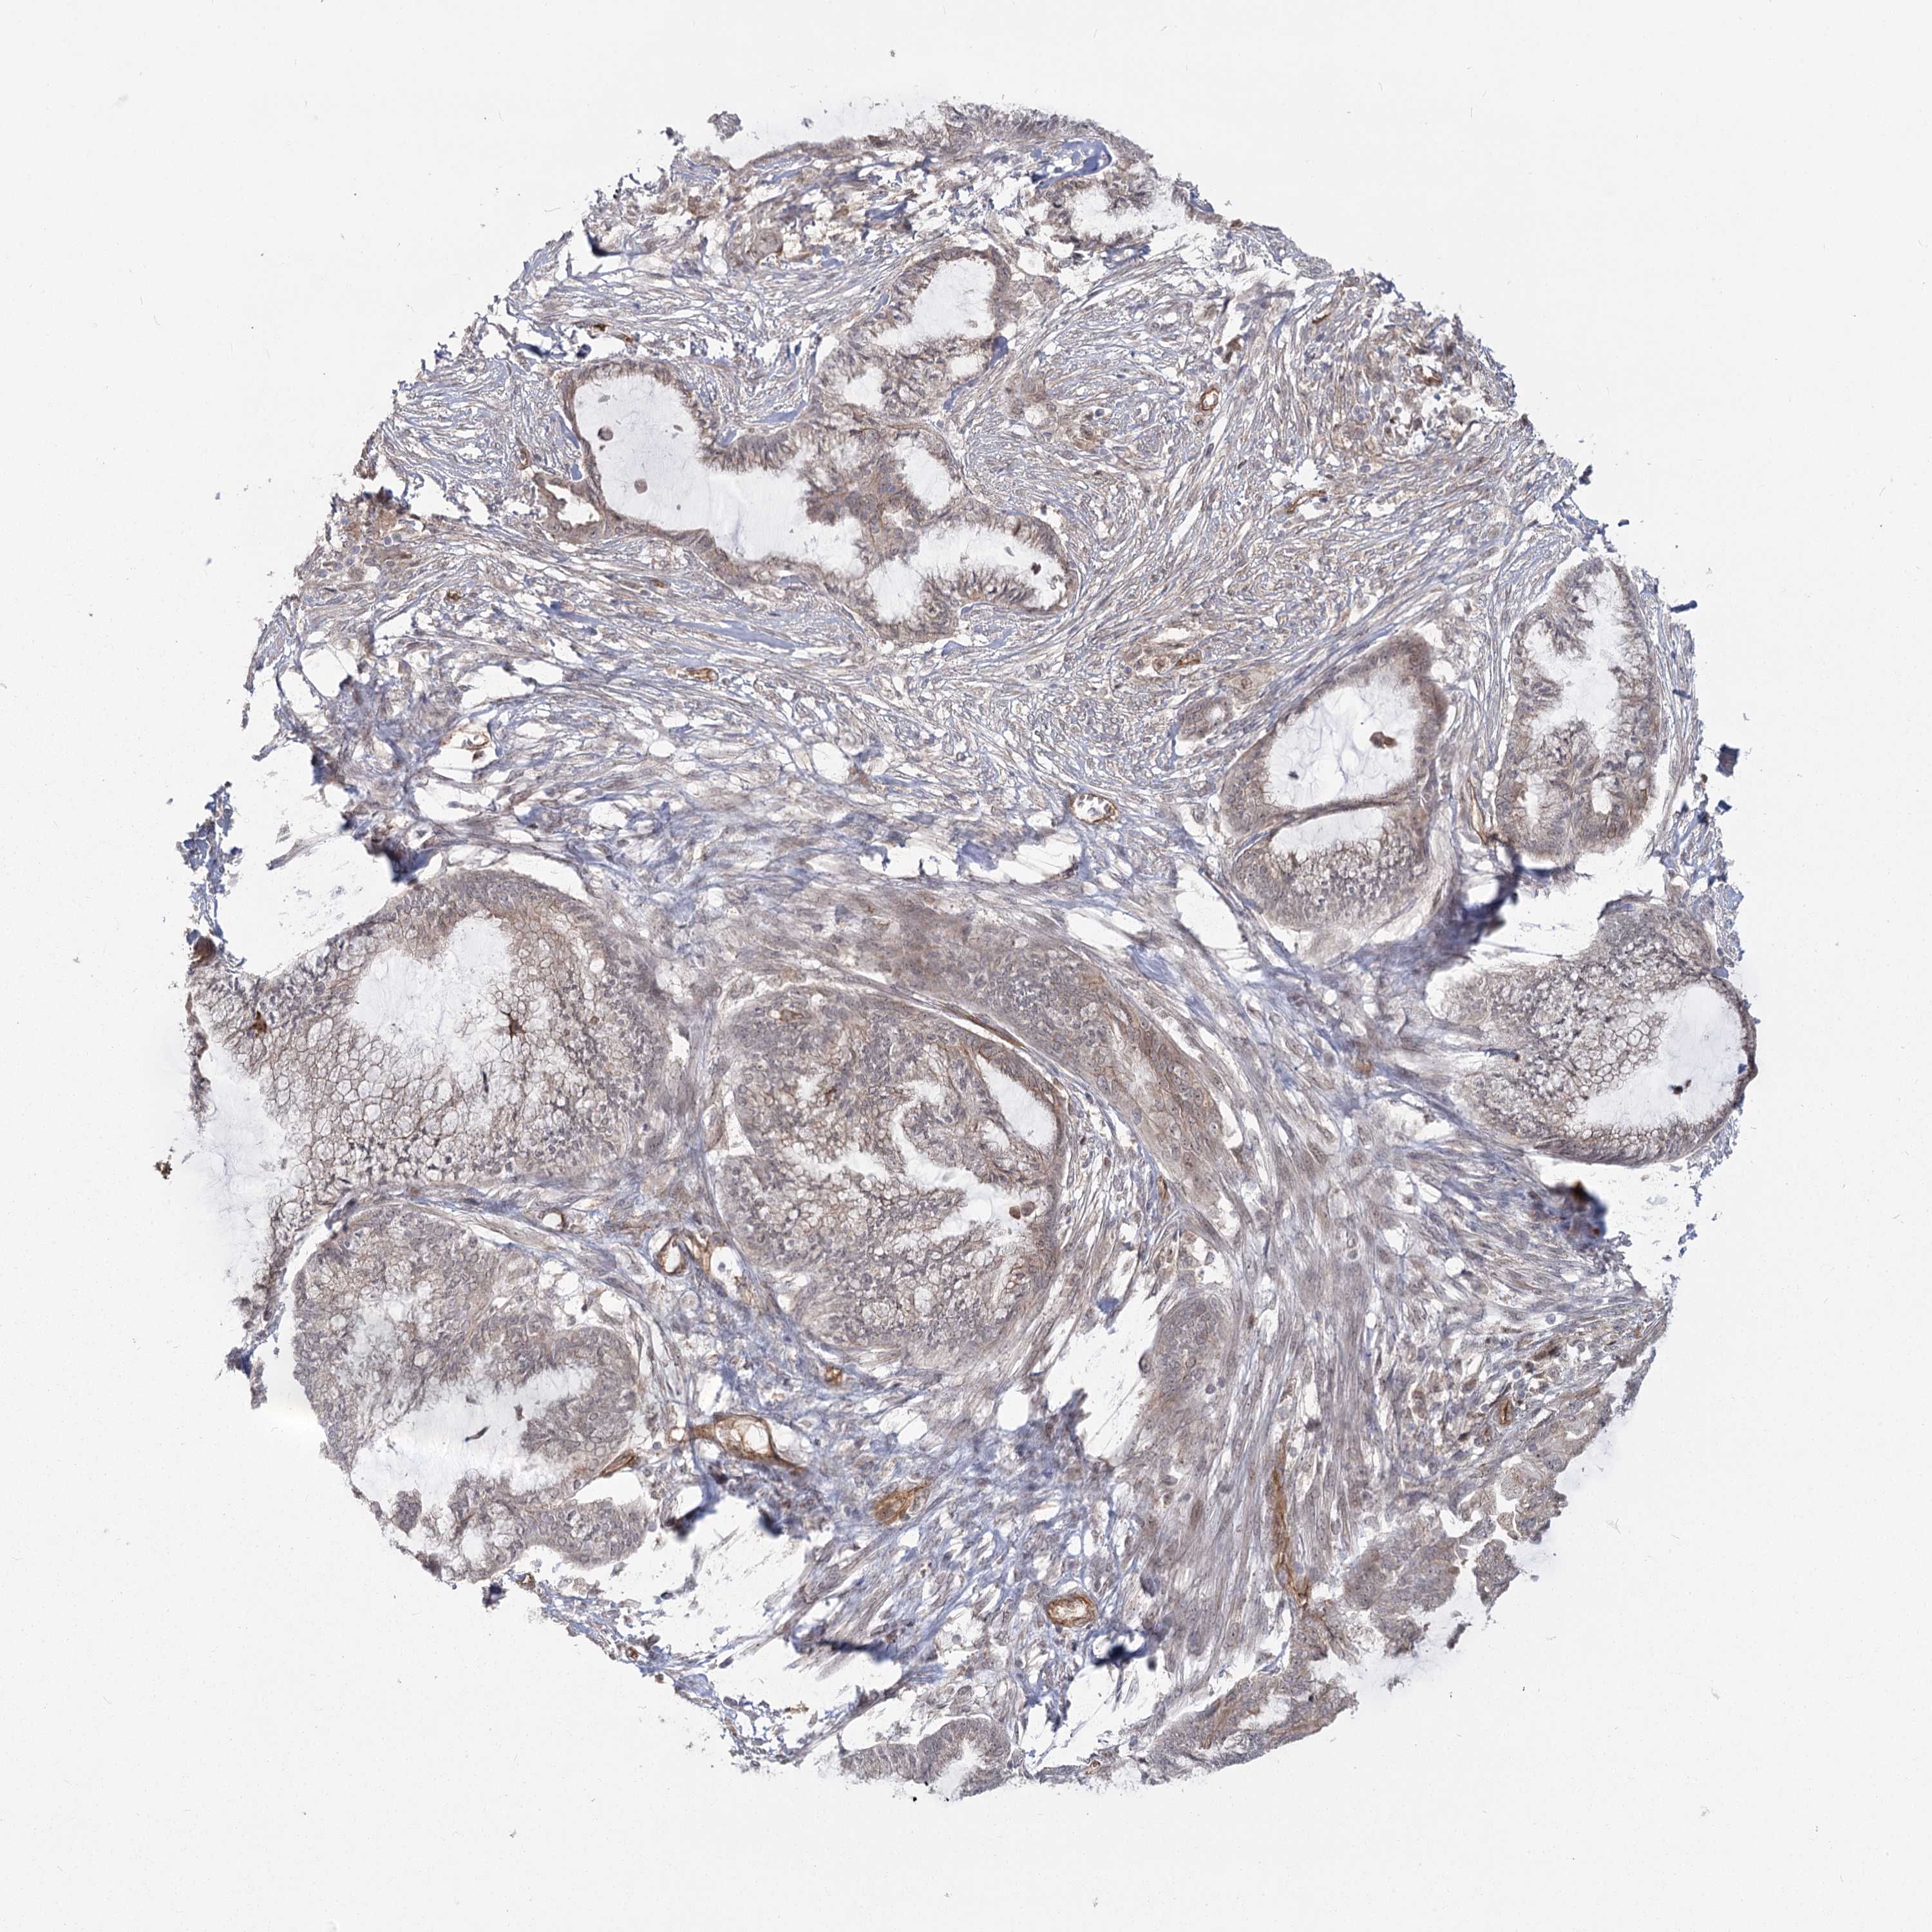

ENDOMETRIAL CANCER - Protein expressioni

A mouse-over function shows sample information and annotation data. Click on an image to view it in a full screen mode. Samples can be filtered based on level of antibody staining by selecting one or several of the following categories: high, medium, low and not detected. The assay and annotation is described here.

Note that samples used for immunohistochemistry by the Human Protein Atlas do not correspond to samples in the TCGA dataset.

Antibody stainingi

Antibody staining in the annotated cell types in the current human tissue is reported as not detected, low, medium, or high, based on conventional immunohistochemistry profiling in selected tissues. This score is based on the combination of the staining intensity and fraction of stained cells.

Each image is clickable and will lead to virtual microscopy that enables deeper exploration of all samples and also displays staining intensity scores, fraction scores and subcellular localization as well as patient and tissue information for each sample.

Antibody HPA036194

Staining

High

Medium

Low

Not detected

Intensity

Strong

Moderate

Weak

Negative

Quantity

>75%

75%-25%

<25%

None

Location

Nuclear

Cytoplasmic/membranous

Cytoplasmic/membranous,nuclear

Adenocarcinoma, NOS

Adenocarcinoma, metastatic, NOS